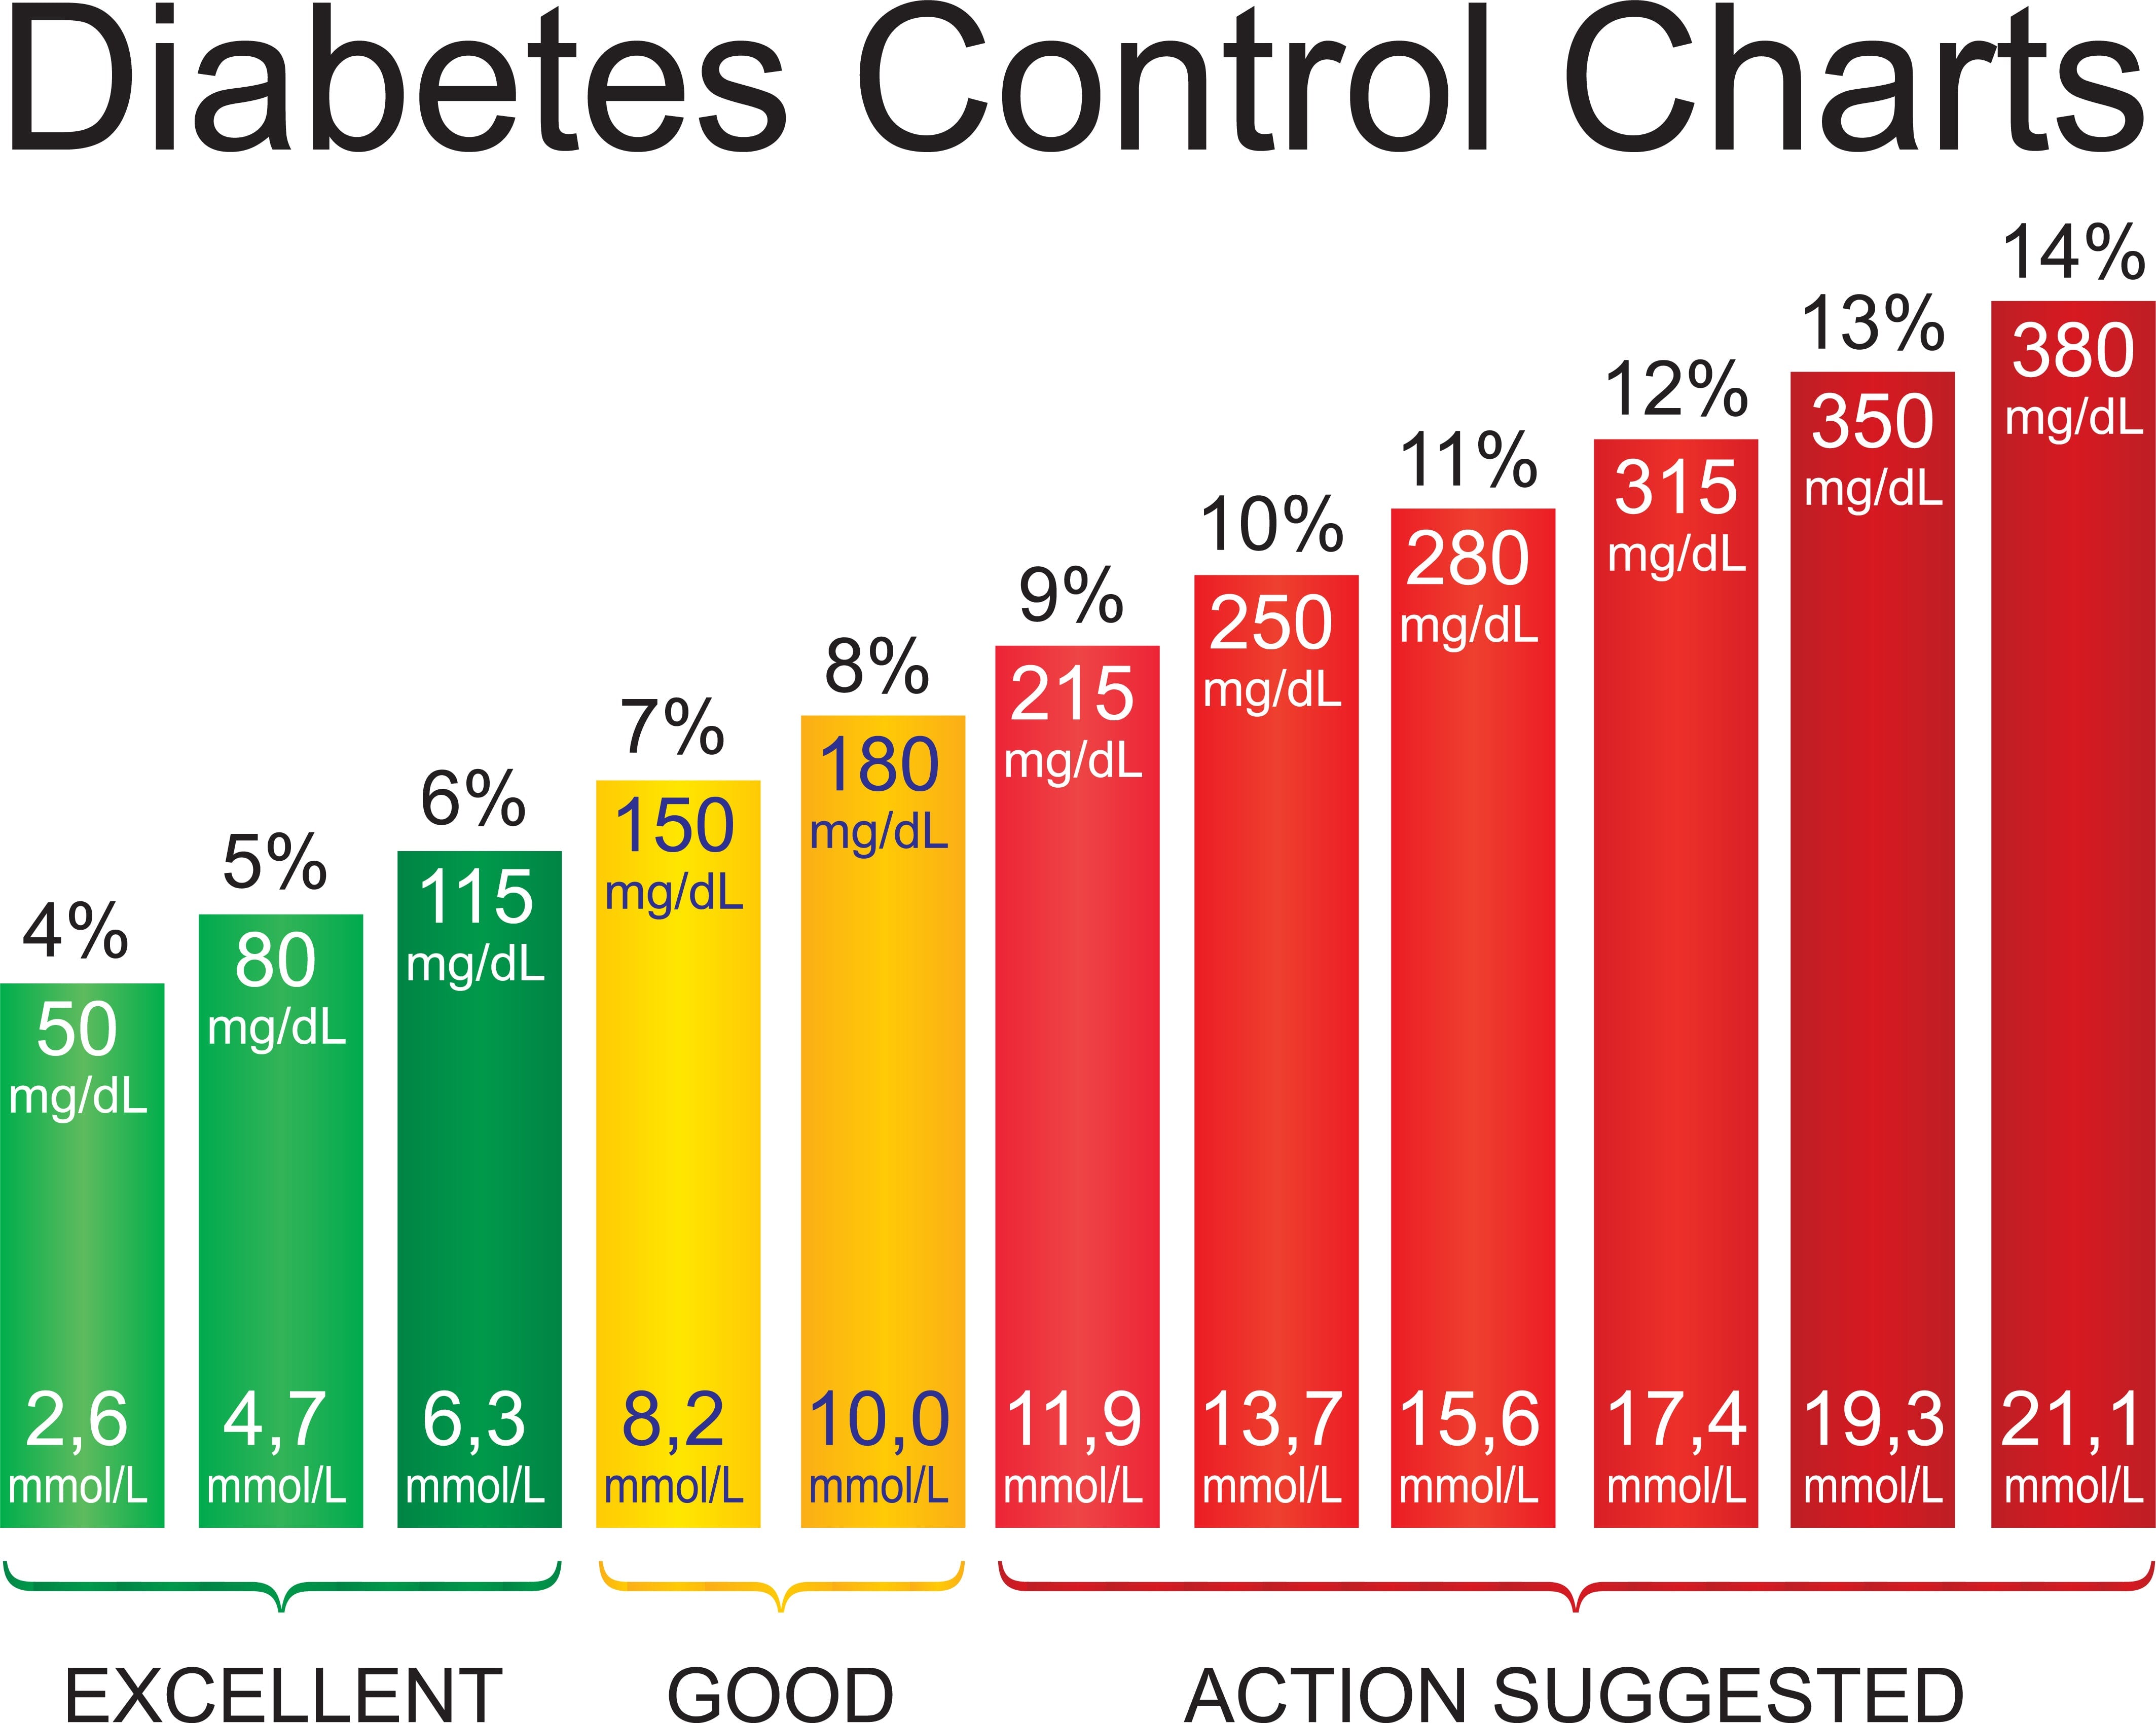

Blood Sugar Chart Understanding A1C Ranges Viasox

http://viasox.com/cdn/shop/articles/Diabetes-chart_85040d2f-409f-43a1-adfe-36557c4f8f4c.jpg?v=1698437113

25 Printable Blood Sugar Charts Normal High Low TemplateLab

25 Printable Blood Sugar Charts Normal High Low TemplateLab